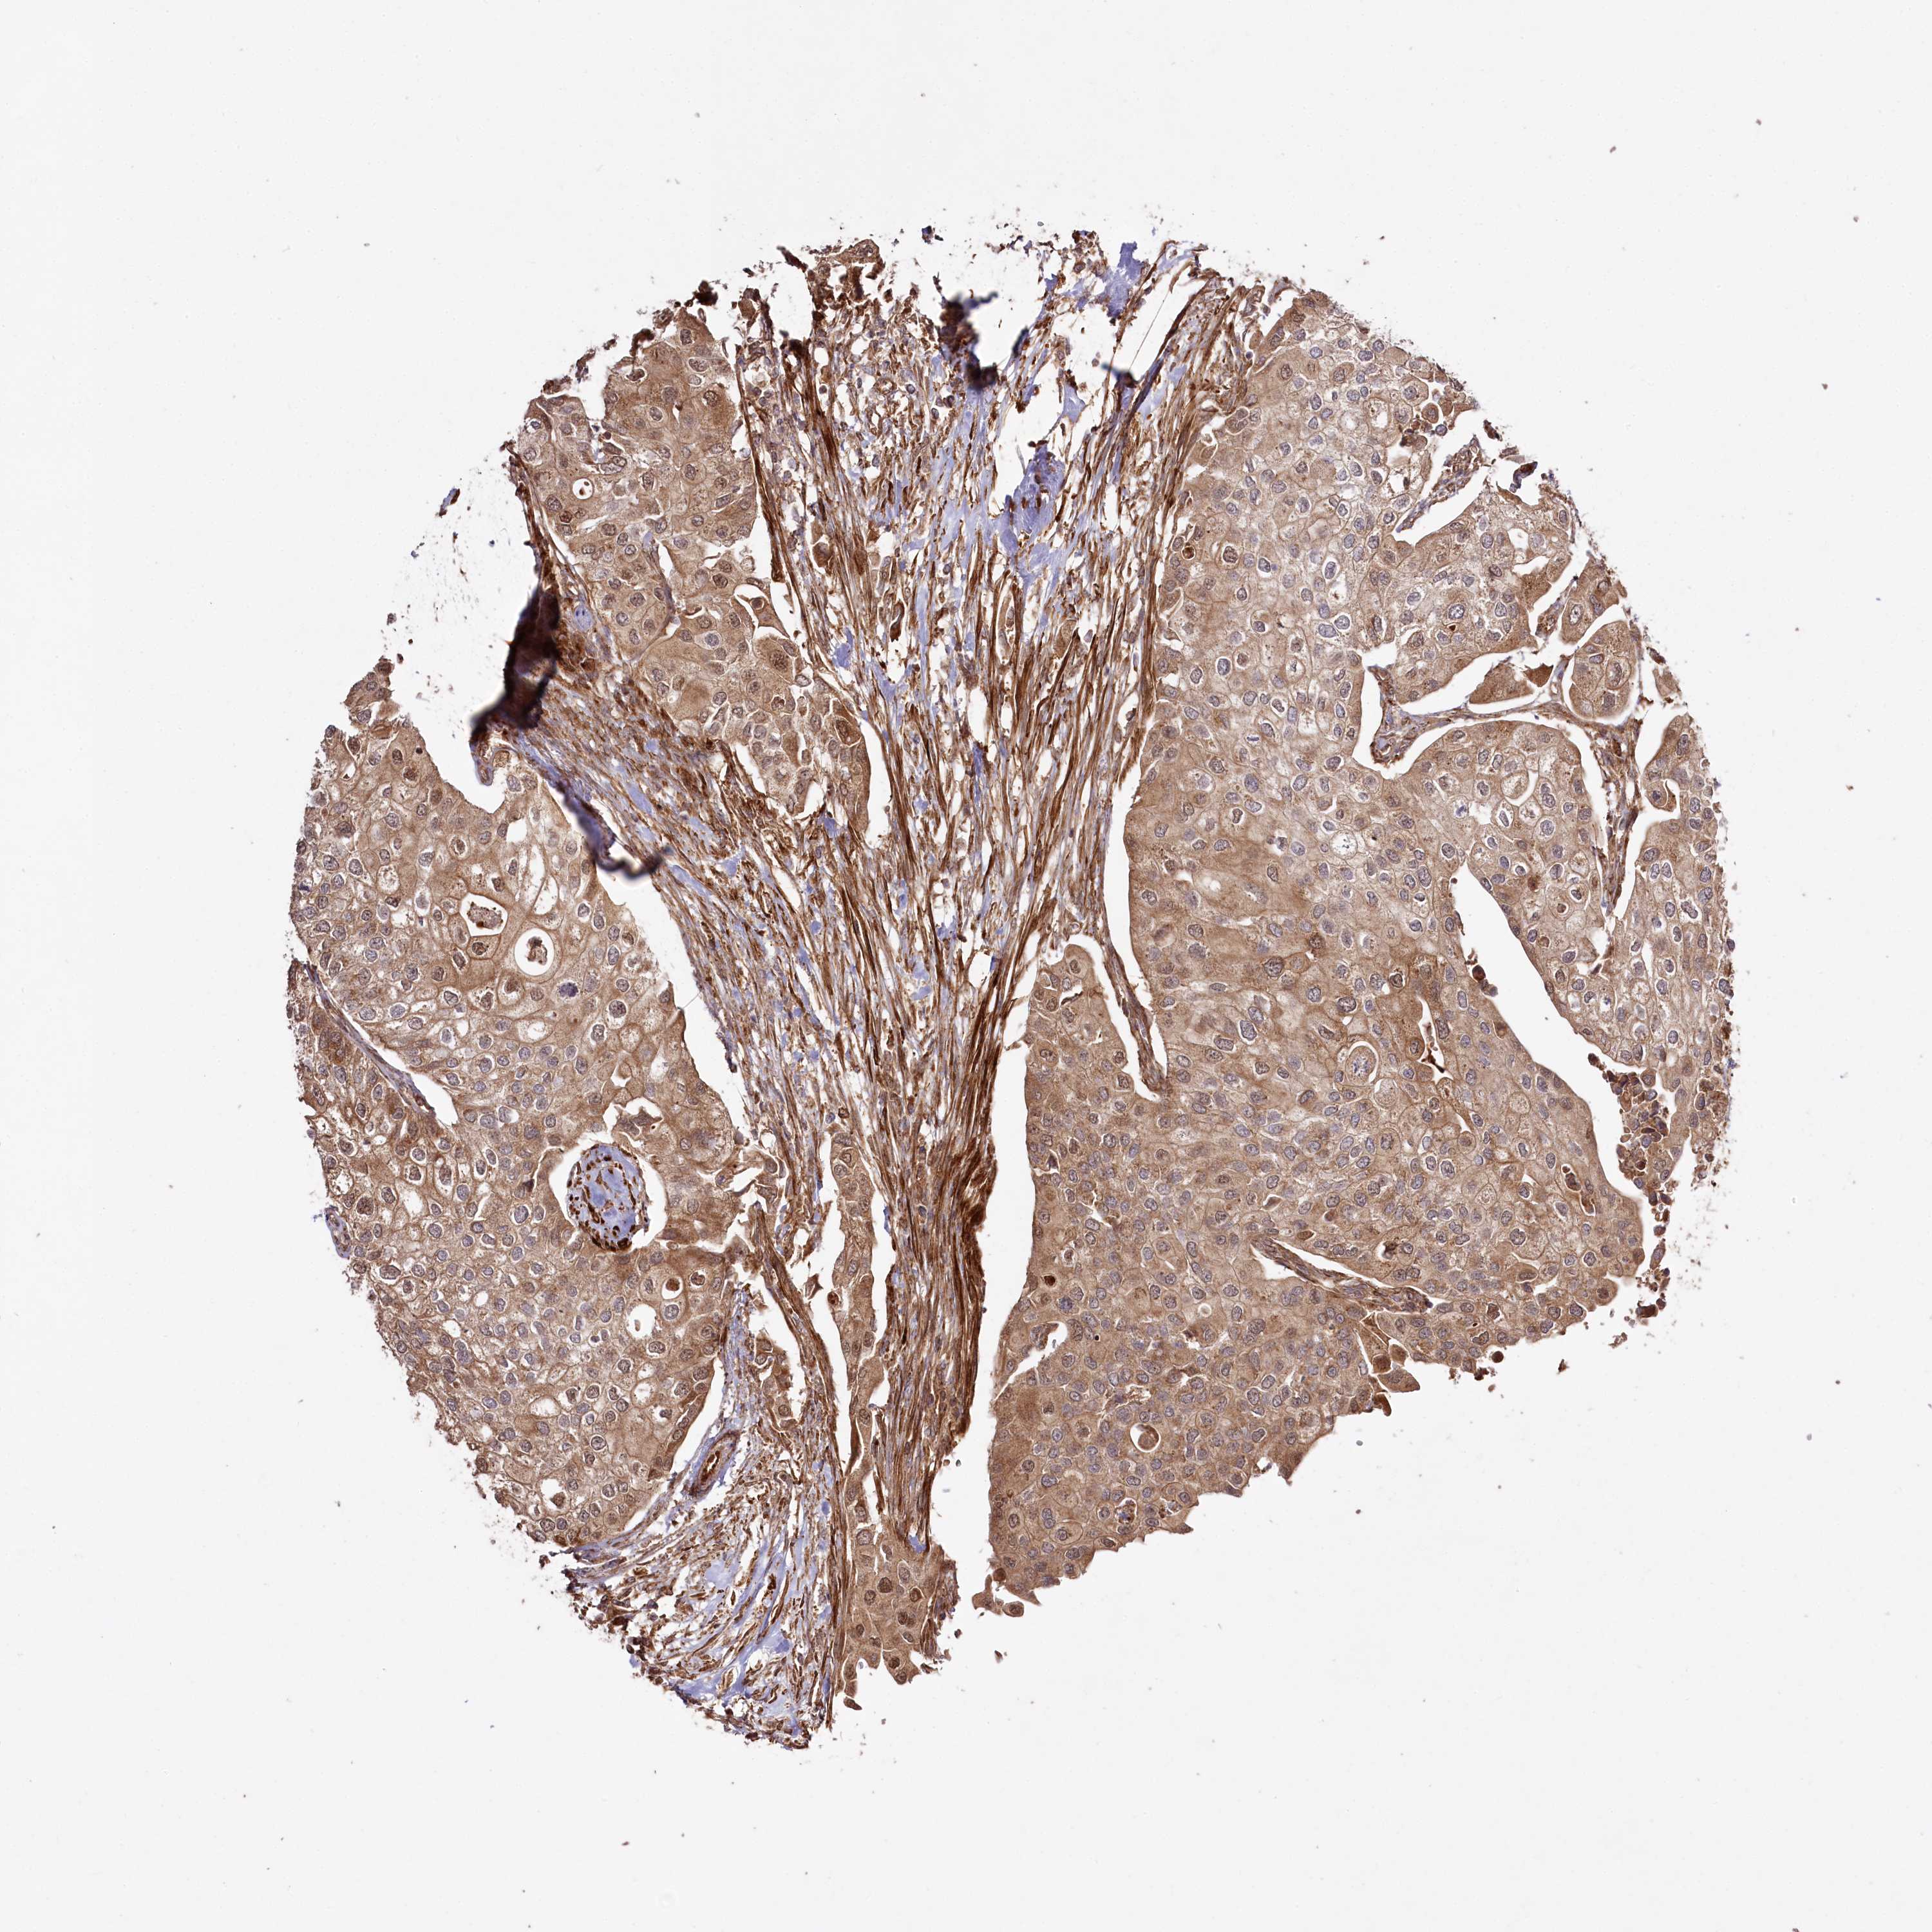

UROTHELIAL CANCER - Protein expressioni

A mouse-over function shows sample information and annotation data. Click on an image to view it in a full screen mode. Samples can be filtered based on level of antibody staining by selecting one or several of the following categories: high, medium, low and not detected. The assay and annotation is described here.

Antibody stainingi

Antibody staining in the annotated cell types in the current human tissue is reported as not detected, low, medium, or high, based on conventional immunohistochemistry profiling in selected tissues. This score is based on the combination of the staining intensity and fraction of stained cells.

Each image is clickable and will lead to virtual microscopy that enables deeper exploration of all samples and also displays staining intensity scores, fraction scores and subcellular localization as well as patient and tissue information for each sample.

Antibody HPA038450

Antibody HPA038451

Staining

High

Medium

Low

Not detected

Intensity

Strong

Moderate

Weak

Negative

Quantity

>75%

75%-25%

<25%

None

Location

Nuclear

Cytoplasmic/membranous

Cytoplasmic/membranous,nuclear

Urothelial carcinoma, High grade

Urothelial carcinoma, Low grade

Urothelial carcinoma, NOS